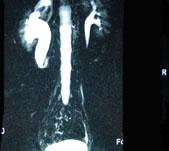

问题 男,20岁,右腰部胀痛不适,MR如图示,下列说法正确的是 ( )

选项 A、考虑为右侧腔静脉后输尿管 B、考虑为右侧输尿管自身的扭曲 C、右侧输尿管上段扩张积水 D、右侧输尿管走行异常,呈“S”形向中线移位 E、右侧肾盂积水

答案 ACDE